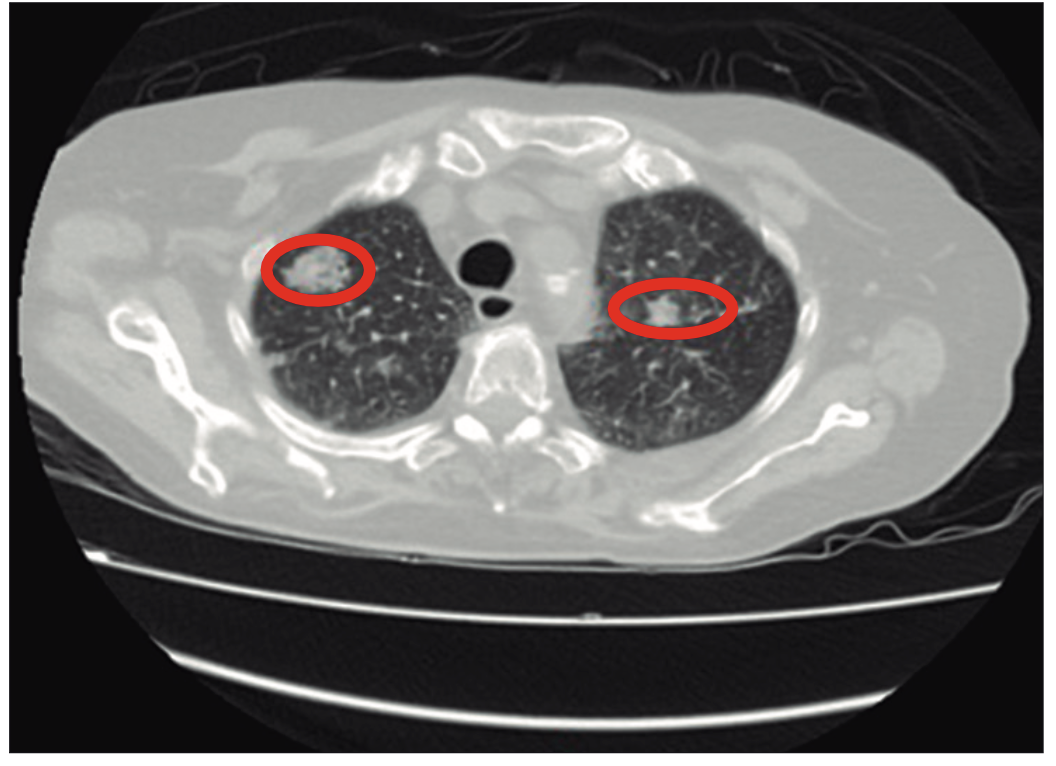

Paciente femenina de 77 años con antecedentes patológicos de HTA y hepatitis autoinmune (anticuerpo ANA y ASMA positivos), sin antecedentes tóxicos y con una historia familiar de cirrosis en su madre. Consulta por debilidad generalizada y dificultad para la marcha. Experimenta debilidad progresiva de una semana de evolución que se intensifica en las últimas 24 horas, con dificultad creciente para la marcha. Durante la evaluación, se constata hiponatremia severa con niveles de sodio sérico de 110 mEq/l. Los exámenes complementarios incluyen una tomografía axial computada (TAC) de tórax que revela múltiples imágenes nodulares pulmonares bilaterales (Figura 3) y derrame pleural bilateral laminar.

Figura 3.

Posteriormente, se realiza una RMN de abdomen con colangiorresonancia que muestra el hígado disminuido de tamaño, con bordes lobulados e intensidad heterogénea difusa, compatible con cirrosis. Se identifican también imágenes nodulares en la glándula suprarrenal izquierda, con diámetros de 13 mm y 20 mm, compatibles con adenomas. Laboratorio: TSH 1,01µUI/mL; T4 1,4 ng/dl. Ionograma urinario de 24 horas: Na 45 m Eq/24 horas, K 70 mEq/24 horas, Cl 150 mEq/ 24 horas. Ecocardiograma: fracción de eyección (FEY) 63%. Examen físico: no presenta edema, ni ascitis, ni ingurgitación yugular. Se indicó reposición de sodio siguiendo protocolos actualizados y tratamiento con antibióticos de amplio espectro, requiriéndose además soporte con vasopresores e intubación orotraqueal con asistencia respiratoria mecánica (ARM). La evolución clínica de la paciente fue tórpida, con desarrollo de shock séptico secundario a urosepsis y óbito. Este caso ilustra la progresión rápida y las complicaciones graves asociadas a la hiponatremia severa en el contexto de hepatitis autoinmune avanzada y enfermedad oncológica no diagnosticada.